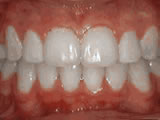

Crowding of the teeth

Before

crowning of teeth

After

Patient started treatment at age 11 and wore braces for 26 months. He loves his new smile.